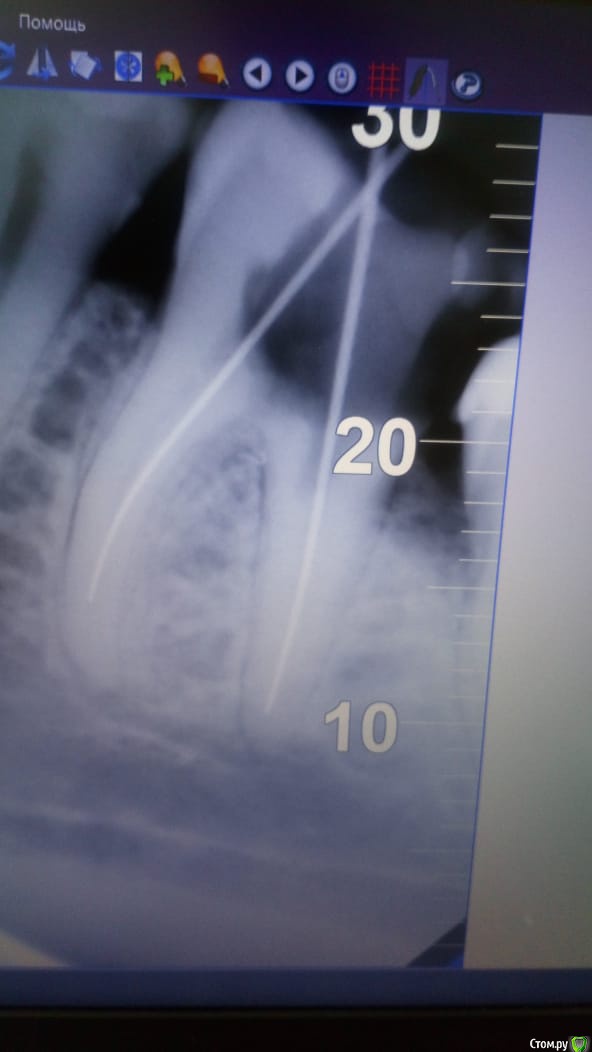

Dassety Опубликовано 10 марта, 2020 Автор Поделиться Опубликовано 10 марта, 2020 Зуб, 5-ка (большой жевательный слева снизу). Снимки прилагаю до склеивания и после. Ссылка на комментарий

Паращук Роман Опубликовано 11 марта, 2020 Поделиться Опубликовано 11 марта, 2020 Ну вы можете обьяснитьпо какой причине? Я ж должна понимать зачем еще раз подвергать жтой всей манипуляции и так треснувший зуб....Он не треснувший,а перфорирован. Трещина дала бы убыль кости между корнями,перфорация,увы,ятрогенная проблема,а значит острая и решаемая с высоким % успеха. Судя по снимку после лечения ваш врач не особо "болел" вашим случаем. Все переделать. Перфорацию обработать и закрыть,каналы перепломбировать. Далее зуб покрыть коронкой. Судя по снимку там адекватному доку делов на два визита. Ссылка на комментарий